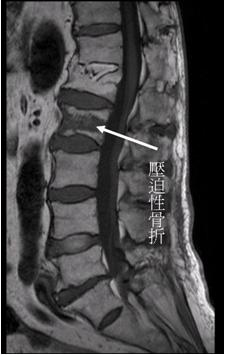

脊椎因為無法承受身體重力而骨折,發生的原因可能是強力外傷所造成的,如從高處跌下。但若是因骨質疏鬆所造成的脊椎壓迫性骨折,大多數只有輕微外傷病史,如走路不慎跌坐,有些甚至無明確外傷病史。症狀是劇烈腰痛或背痛,特別是在起床或翻身活動的時候,靜臥休息則可以減緩。骨質疏鬆所造成的脊椎壓迫性骨折容易發生在老年人,特別是在停經後的婦女。患者的初步檢查如X光呈現骨折的脊椎體變得比鄰近正常椎體扁,若要進一步診斷需靠磁振造影檢查,確定X光呈現的椎體變扁是新的壓迫性骨折,而且確定沒有其他原因造成椎體骨折,如感染或惡性腫瘤。

上圖為患者磁振造影,顯示第二節腰椎訊號顯示異常,代表是新發生的壓迫性骨折。 (第一節雖更扁,但訊號顯示是陳舊性,不需治療)。 |